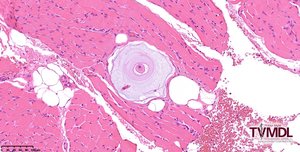

Texas A&M Veterinary Medical Diagnostic Laboratory (TVMDL) diagnosed canine hepatozoonosis in a muscle biopsy from a 3-year-old dachshund-mix dog. The patient was reported to have non-specific clinical signs with a neutrophilic leukocytosis and a WBC of 50,000. The submitting veterinarian sent formalin-fixed punch biopsies from the triceps and semitendinosus muscles to TVMDL. Histopathology revealed a mild granulomatous myositis with scattered onion-skin cysts characteristic of H. americanum.

These parasites are often widely distributed throughout all skeletal muscle. Since they can be scattered through the tissue, submission of multiple biopsy specimens is recommended to increase the chance of collecting a diagnostic sample. Histologically, organisms can be found in skeletal and cardiac muscle and may be accompanied by pyogranulomatous inflammation. The parasites are often surrounded by multiple layers of mucopolysaccharide, creating a characteristic “onion-skin” cyst,